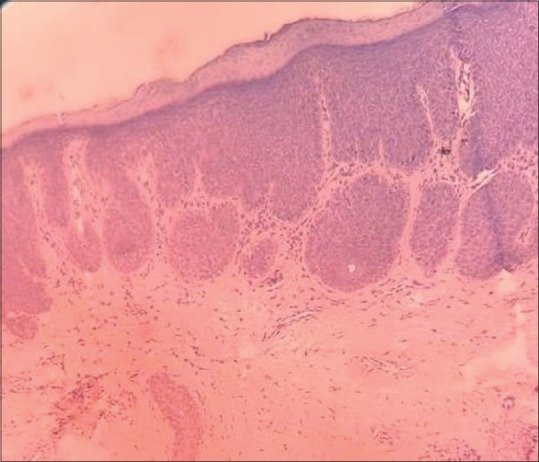

Inflammatory linear verrucous epidermal nevus (ILVEN) is a variant of keratinocytic epidermal nevi. In contrast to noninflammatory epidermal naevi, ILVEN is less common, typically erythematous, and persistently pruritic. It usually appears at birth or in early childhood and follows a linear distribution along Blaschko's lines. Genital or perigenital involvement is relatively rare. We report a case of ILVEN on the labia majora of an 11-year-old female. ILVEN usually presents on extremities and trunk, but is uncommon on the genitalia.